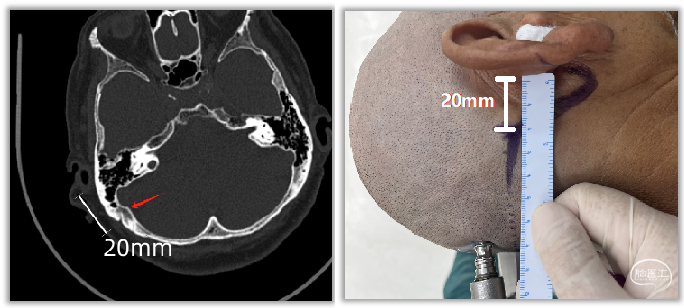

1.神经内镜的应用

MVD术中应用神经内镜有助于责任血管的判断、评价神经根部减压情况及垫棉的大小和放置位置等。国内部分医院已开展全内镜MVD手术,笔者在此进行简要介绍(以右侧为例,开颅过程同前):

内镜的局部放大和良好的照明能弥补手术显微镜管状视野的不足,不需过多牵拉和剥离神经组织即能清晰地显露REZ区并放置垫棉,对提高手术治疗效果、减少症状复发和并发症发生有一定临床意义,并使锁孔入路手术变得更加可行。

但在目前的技术条件下,不提倡全面推广全内镜下MVD。尤其对于脑脊液释放后小脑外侧池仍然狭小、且小脑绒球突出的患者,不应勉强实施全内镜手术,应以患者安全为首要前提。

全内镜MVD只是一项技术手段,从目前的照明、成像和手术器械角度而言尚无法完全取代显微镜MVD手术。临床应用应由患者后颅窝解剖条件、术者手术技术特点等多方面因素综合考量决定。